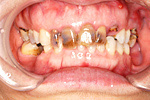

症例 6

① 虫歯でぼろぼろの歯は抜きます。

② 歯の無いところはインプラントで補います。

60才代 女性

総額:300万円(税別)

治療期間:1年6ヵ月

リスク副作用:清掃不良ですと歯周痛が再発します。セラミックが欠けることがあります。